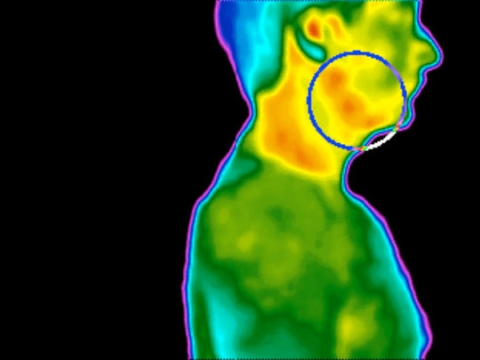

A termografia aplicada à acunpultura

As primeiras publicações propondo a aplicação da Termografia em acupuntura e medicina chinesa surgiram no final da década de 70. A primeira publicação citada (...)

Termografia é uma técnica que diagnóstico que usa imagem das ondas infravermelhas emitidas pelo organismo para formar uma imagem da temperatura superficial da pele humana. A fotografia infra-vermelha foi inventada na época da II Guerra Mundial com intuito de identificar (...)